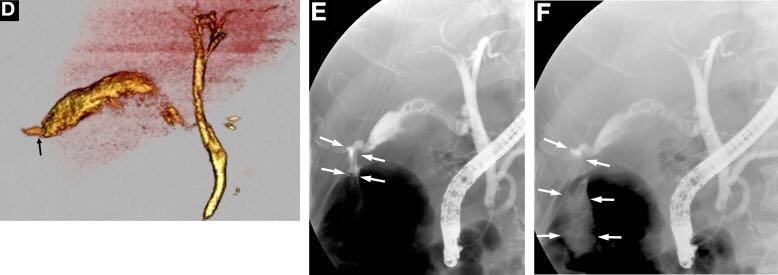

通过CT在胆道内没有观察到明确的穿孔部位。然而,伴随对胆道穿孔的怀疑、进行三维滴注CT胆道造影,显示泄漏的造影剂从胆囊底(图D,箭头)进入肝下间隙,引起自发性胆囊穿孔的诊断。内镜逆行胰胆管造影证实在同一部位有穿孔(图E、F,箭头)。放置内镜鼻胆管引流管,并持续引流胆汁。四周后,患者的一般情况稳定后进行胆囊切除术。组织学检查显示胆囊底有3mm穿孔,伴随与慢性胆囊炎引起的胆囊底部明显坏死。没有发现结石。患者顺利康复,最终病情好转出院。 胆囊穿孔是一种罕见但危及生命的胆囊炎并发症,伴或不伴结石,最近报道的死亡率为9.5%。[1]Niemeier[2]将该疾病分为3种类型:I型(急性),无穿孔和弥漫性腹膜炎;II型(亚急性)、局限性腹膜炎、胆囊周围脓肿;III型(慢性),胆囊肠瘘。这种分类仍在使用中。这名患者为I型穿孔。最常见的穿孔部位是胆囊底部,因为此处血液供应不畅。自发性胆囊穿孔的诱发因素包括感染、胆石症、糖尿病、动脉粥样硬化和类固醇激素治疗。超声,CT,磁共振成像,内镜逆行胰胆管造影术或胆道造影提示了该诊断。 如在本案例中观察到的,滴注CT胆道造影提供了胆道系统的高质量图像;然而,在一些国家静脉胆管造影介质的可用性是有限的。[3]诊断的困难造成治疗延误,导致高发病率和死亡率。胆囊穿孔应被视为不明原因腹膜炎患者的鉴别诊断。